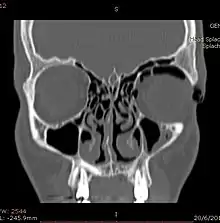

Computed tomography (CT)

CT scan taken from the transverse plane demonstrating orbital emphysema.[39]

CT scan taken from the coronal plane demonstrating orbital emphysema.[39]

Computed tomography is effective and sensitive in the diagnosis of orbital emphysema,[3][37] as it can confirm the anatomical location and size of air, bony defects, indentation of the eyeball, and the condition of the optic nerve, as well as the presence of any extraocular muscle entrapment and herniation of preorbital fat into the sinus cavities.[3][15][38] The location of the orbital emphysema is present near the site of the fracture.[1][3] The scans are usually taken along the transverse plane. Transverse images allow the evaluation of fractures in medial and lateral orbital walls. By reformatting these transverse images or taking coronal images, the examination of orbital floor and roof is permitted. Helical scanning is preferred as it has a lower imaging time and radiation dose comparing to conventional scanning, especially when reforming transverse helical scans into coronal images.[3] The staging of orbital emphysema can then be determined with visual acuity examination and ophthalmoscopy.[6] A disadvantage of using a CT scan is that when detecting air after orbital trauma, the presence of a wooden foreign object can give a false positive result of orbital emphysema. The wooden object can mimic the presence of orbital emphysema. Therefore, patients’ medical history is crucial in making the correct diagnosis.[3]